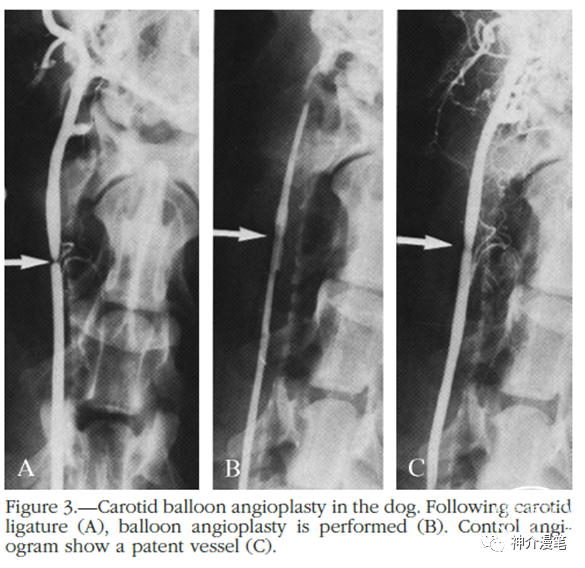

说到颈动脉支架,不得不隆重介绍一下下面这位大神,德国弗莱堡的Klaus Mathias教授。70年代末,他率先在狗身上建立了颈动脉狭窄的模型并使用9F球囊导管进行扩张实验。接下来当然就是想着在人身上小试牛刀了。但是他的这一想法遭到了当时德国血管外科协会的强烈反对,认为其有较高的引发卒中的风险,而且CEA手术当时已经非常成熟。因此,大家一致投票否定了Klaus的念想。

但是大神终归是大神,决不放弃自己的初衷,不忘初心,方得始终。还是被他逮到了机会,

1979年,Klaus Mathias在一位32岁的肌纤维发育不良的女性颈内动脉首次进行球扩成型。能抓住这个病例的原因是血管外科认为手术风险不确定而拒绝给这位患者进行手术。操作过程为:猎人头导管陪0.035导丝,到位后交换4*40球囊,无导引导管等支撑。人类史上首次的颈动脉球囊扩张术诞生了。1980年,他首次给一名68岁的粥样硬化性狭窄患者进行球扩成型术中没有造影指引,根据骨性标志“盲扩”。手术效果都很不错,可以说是技惊四座。

大神的脚步永不会停歇。1989年,Klaus Mathias在一位65岁患者的球扩时出现内膜撕脱。使用10*40的Wallsent支架进行补救。第一个颈动脉支架诞生了。需要提醒大家注意的是,在当时的年代,该支架是用于胆管手术的,并非为了颈动脉而生。当然我到现在也认为这是大神蓄谋已久的计划,而非偶然临时起意。在此后的十年间,逐渐意识到介入手术这玩意也还靠谱的人们,开始大量尝试介入治疗颈动脉狭窄,而球扩支架Palmaz成为了颈动脉支架的主力军。